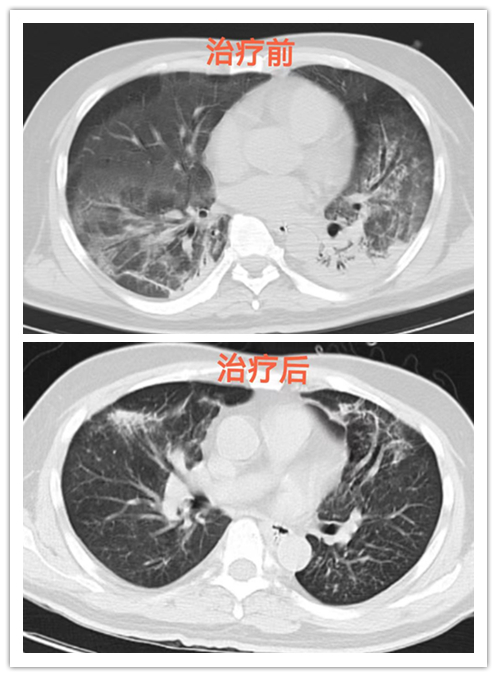

在转入呼吸ICU后的第二天,患者病情发展进入上升期,严重的感染和呼吸衰竭,脓毒性休克、炎症风暴、持续的高热寒战、肝功能不全、电解质紊乱等病症,随时威胁着患者的生命。这种脓毒性休克、全身炎症反应综合症和急性呼吸窘迫综合征等多重严重病症叠加,死亡风险非常高。在抗感染、腹腔引流脓液和保护性肺通气策略的机械通气支持等综合治疗下,患者的血氧饱和度开始有所改善,体温也较之前下降,全身感染有好转。通过积极有效的调整治疗方案后,在插管后的第八天,患者病情明显好转,予以拔除了气管导管吸氧气治疗。目前,患者病情平稳,已康复出院。